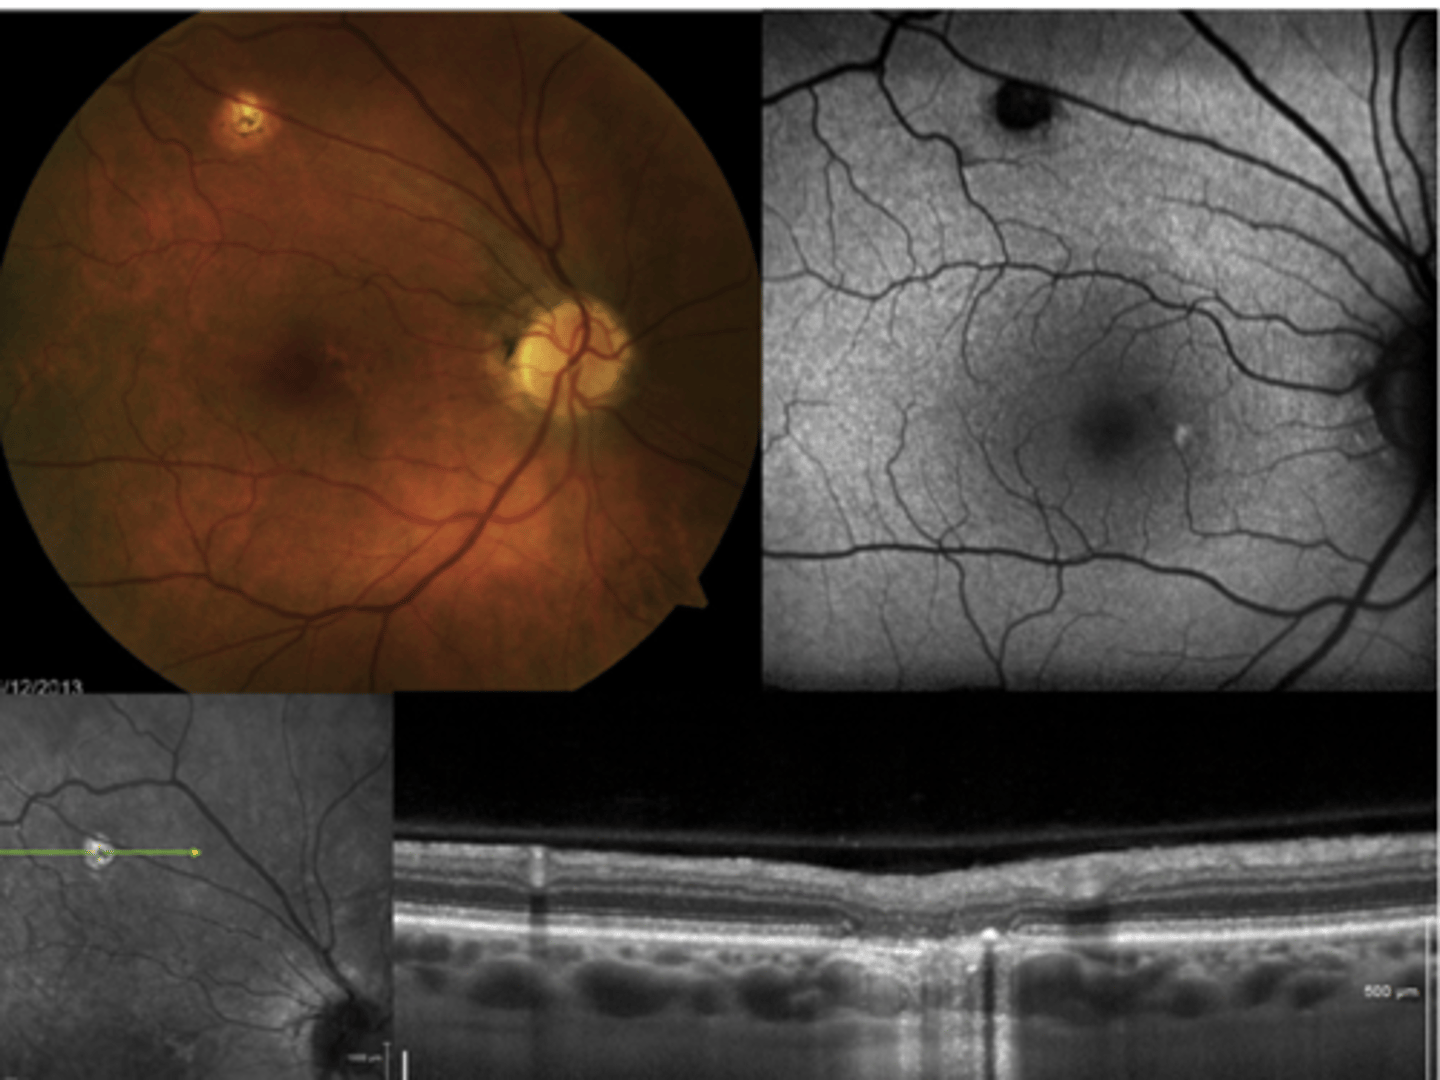

How does choroidal rupture appear on OCT here?

loss of RPE continuity at site of rupture = inner choroid atrophy

How does choroidal rupture appear on OCT here?

RPE disruption

+/- hemorrhage

How does choroidal rupture appear on FAF?

hypoAF where RPE is atrophied